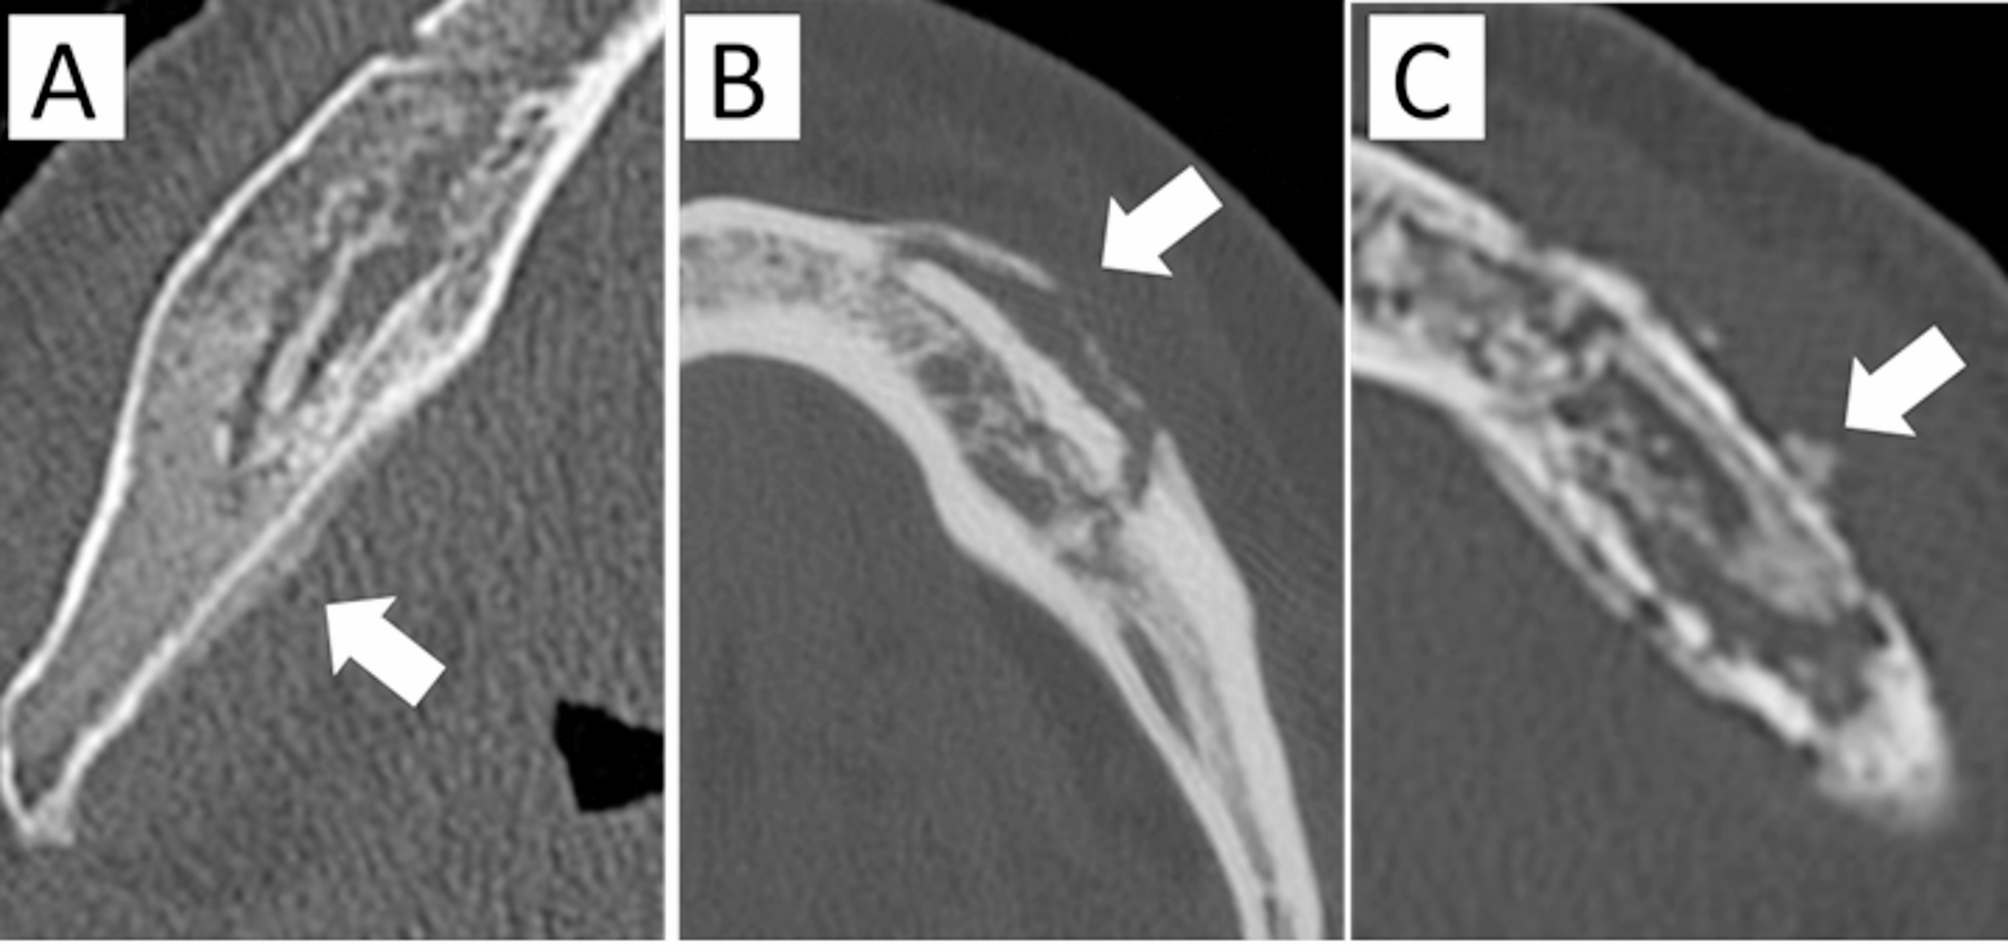

Fig. 3

Periosteal reaction.(A) Attached type—new bone is formed parallel to the mandible, without a gap(arrow). (B) Gap type—new bone is formed parallel to the mandible, separated by agap (arrow). (C) Irregular type—new bone is formed with an irregular shape(arrow).